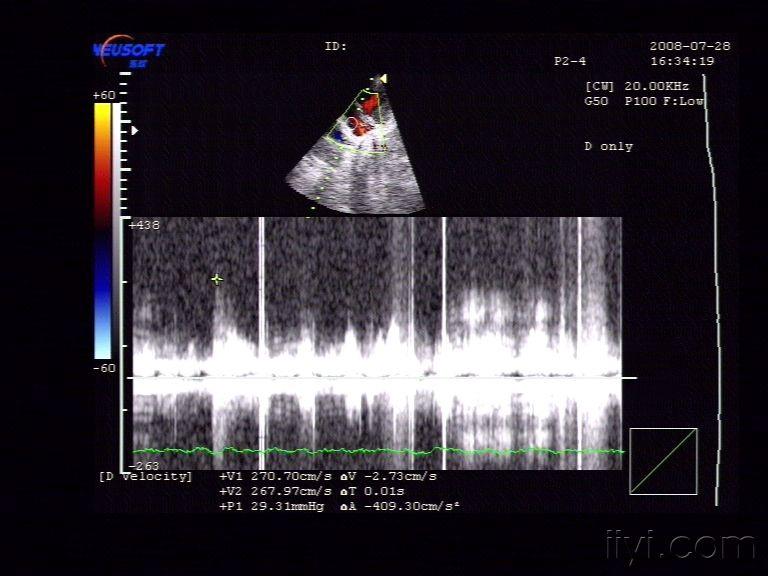

原发性房间隔缺损 - 超声医学讨论版 - 爱爱医医学论坛

图片尺寸640x480